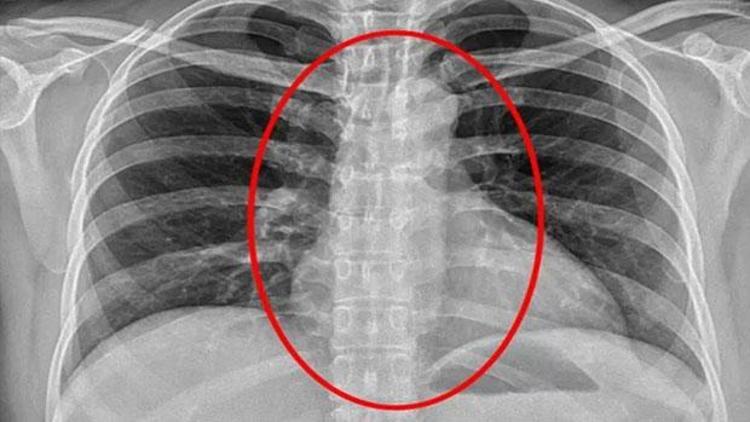

Operasyonun ardından kontrol için hastaneye kaldırılan kadının röntgeni çekildi ve göğsünde bir gölge belirlendi. Güvenlik güçleri gölgenin kadının yuttuğu kondomdan kaynaklandığını düşünüyor.